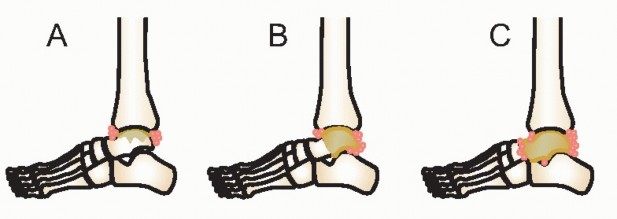

DEFINITION AND INTRODUCTION Patrick Haglund in 1928 described an enlarged posterior border of the os calcis. …